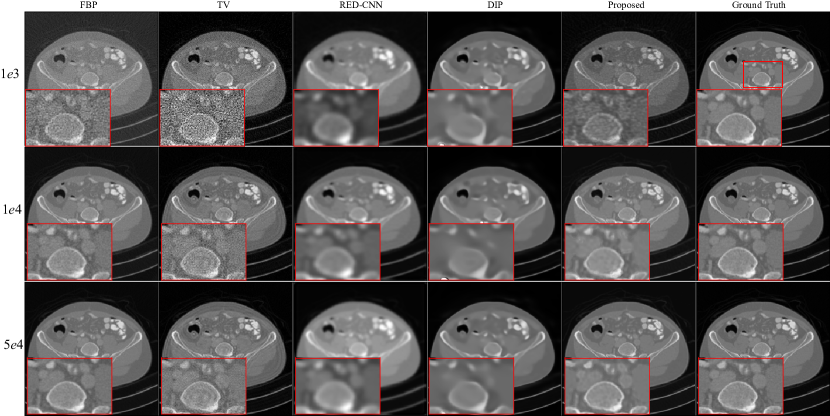

Figure 5: Reconstruction results of LoDoPab-CT data at different dose levels by different methods. Zoomed ROI images from the ground-truth image.

LoDoPab-CT data: For the LoDoPab-CT data, the reconstruction results are shown in Fig. 5. From Fig. 5, we can observe that the performance of each reconstruction method is similar to their performance for the above AAPM challenge data reconstruction. The reconstructed results by FBP and TV suffer from noise and artifacts, although TV can suppress a lot of noise. The textures and edges in the reconstructed results by RED-CNN are smoothed out, whereas DIP can remove noise and preserve tiny structures more effectively. The proposed method achieves the best performance with regard to noise suppression and preservation of tiny structures. Furthermore, the reconstruction errors (Fig. 6) further demonstrate that FBP method sacrifices a lot of useful information. TV and RED-CNN can effectively improve the reconstructed results by FPB; however, TV can not preserver edges well, and RED-CNN tends to smooth edges and textures. DIP has slighter residual errors in terms of edges and textures. Compared with the competitive methods, the proposed method significantly decreases the reconstruction errors by FBP and achieves minimal reconstruction errors.